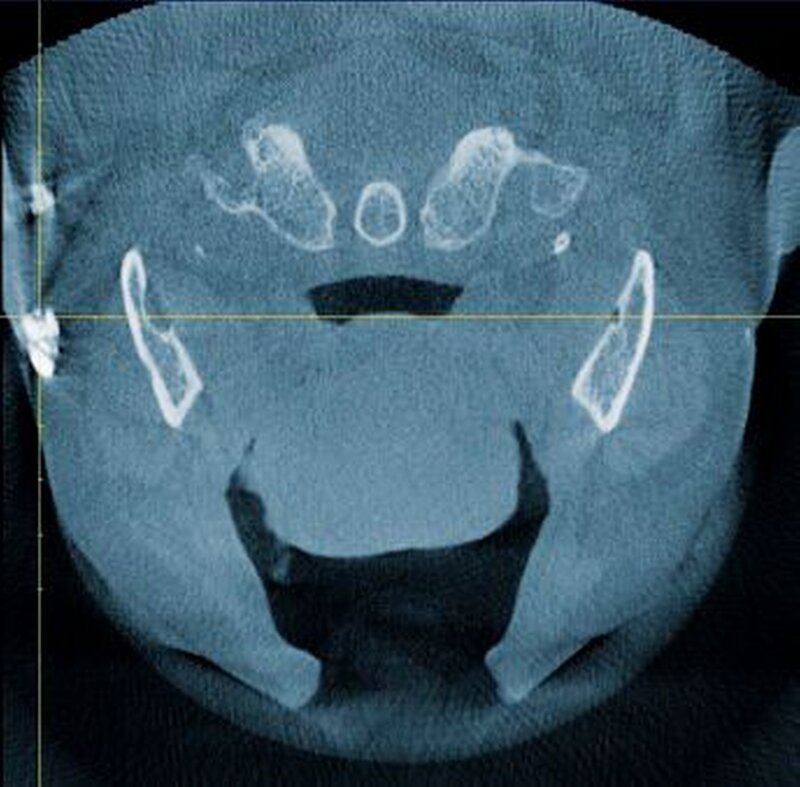

Zur genauen räumlichen Zuordnung der Verschattungen unterhalb der Incisurae semilunares wurde eine dentale digitale volumentomografische Untersuchung durchgeführt (Abbildungen 2 bis 4).